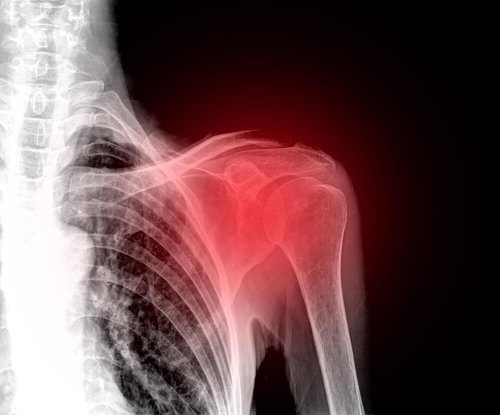

Болката в рамото е много неприятно и болезнено състояние, тъй като раменната става ви позволява да бъдете активни и да контактувате с околната среда. Различни видове травми водят до появата на болка, подуване и обездвижване. Оттокът на рамото може да стане хроничен, ако не получите адекватна медицинска помощ.

Първо трябва да имате в предвид, че болката в рамото се среща много по-често отколкото си мислите. Трябва да посетите лекар, ако се касае за разместване или фрактура на рамото. Тези две състояния най-често се появяват в резултат на травми в тази област.